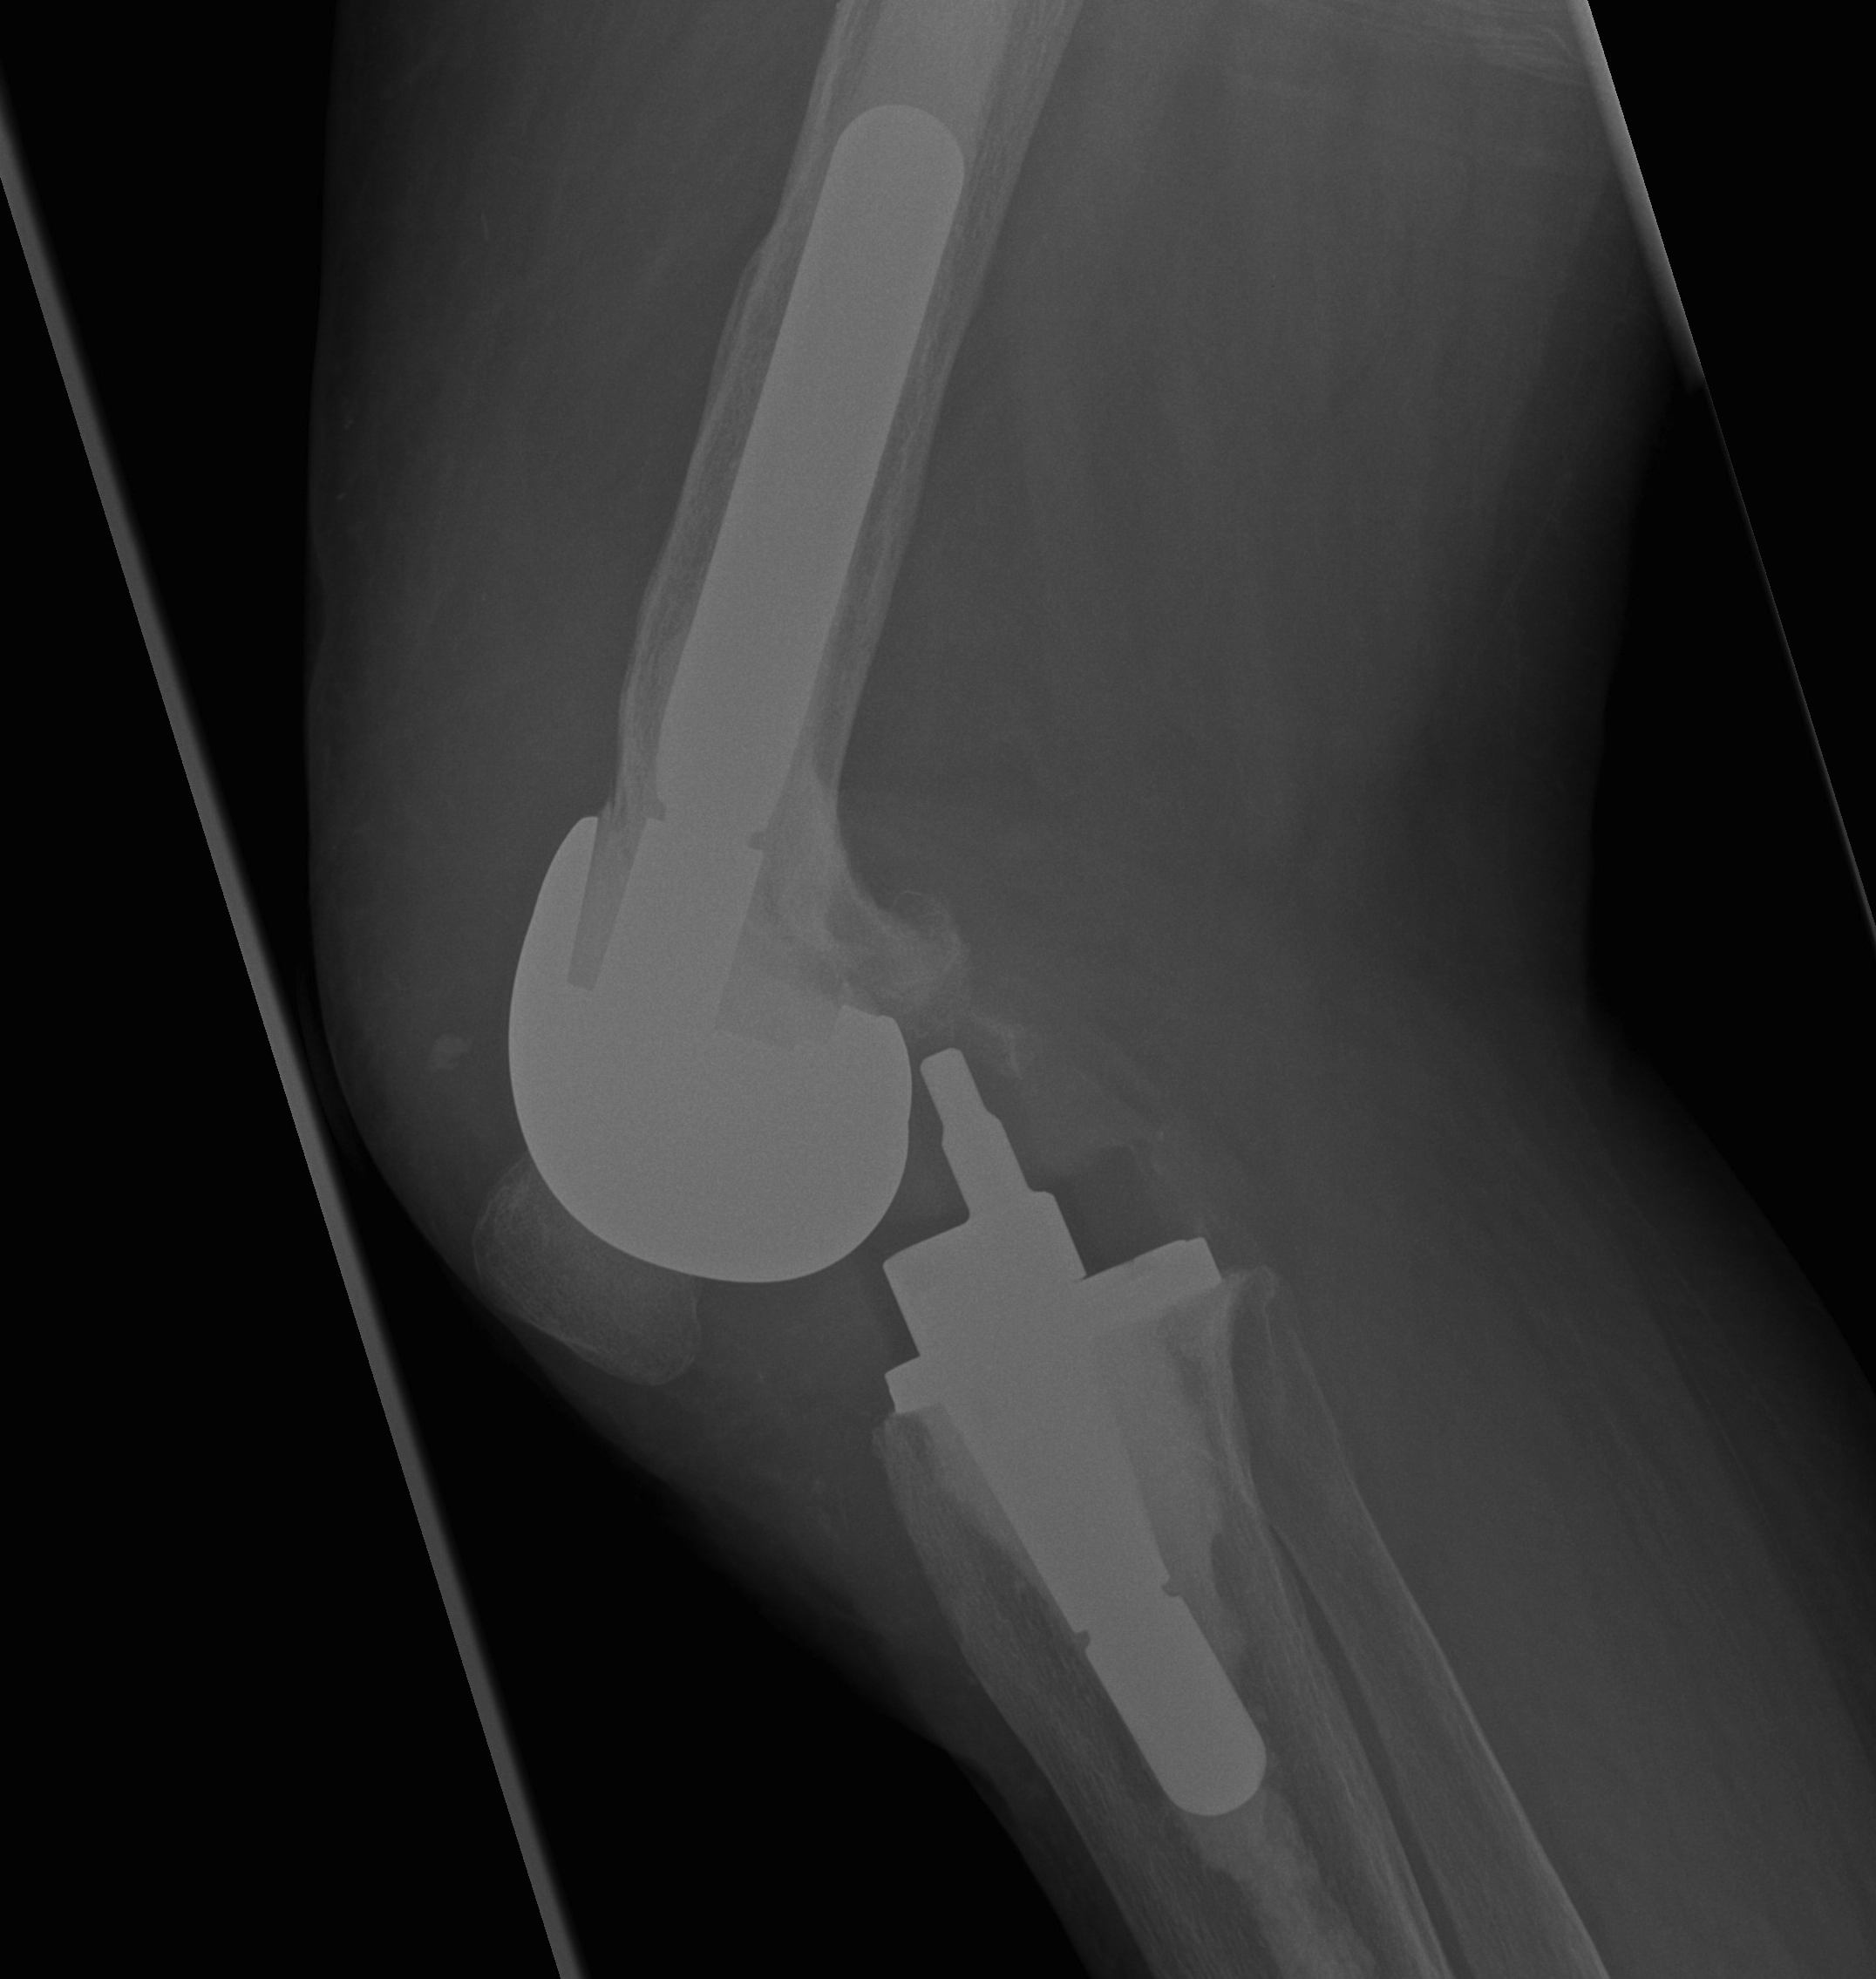

- 184 cemented revision TKR with press fit stems

- significant bone loss

10. Loosening